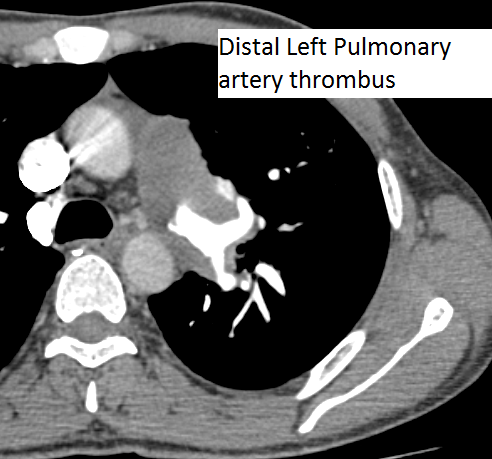

The authors present a case of CTEPH. The patient was a 35-year-old man presenting as an outpatient with complaints of severe progressive dyspnea. He was diagnosed with pulmonary embolism in the past and has been on anticoagulation for more than three years. He has had CT scans and chest x-rays in between. Multiple transthoracic echocardiograms have been performed with evidence of slowly declining right ventricular function. This time, he presented to the cardiac surgery service with a severely dilated and dysfunctional right ventricle. He had been on diuretics and vasodilator treatment but had mild to no improvement. After a thorough review, the authors decided to perform a pulmonary thromboembolectomy. The CT scan images show a dilated RV and intravenous contrast reflux in the inferior vena cava (Figures 1-4). The thrombus can be seen starting in the main pulmonary artery and almost completely occluding it. The thrombus extends into the bilateral pulmonary arteries.